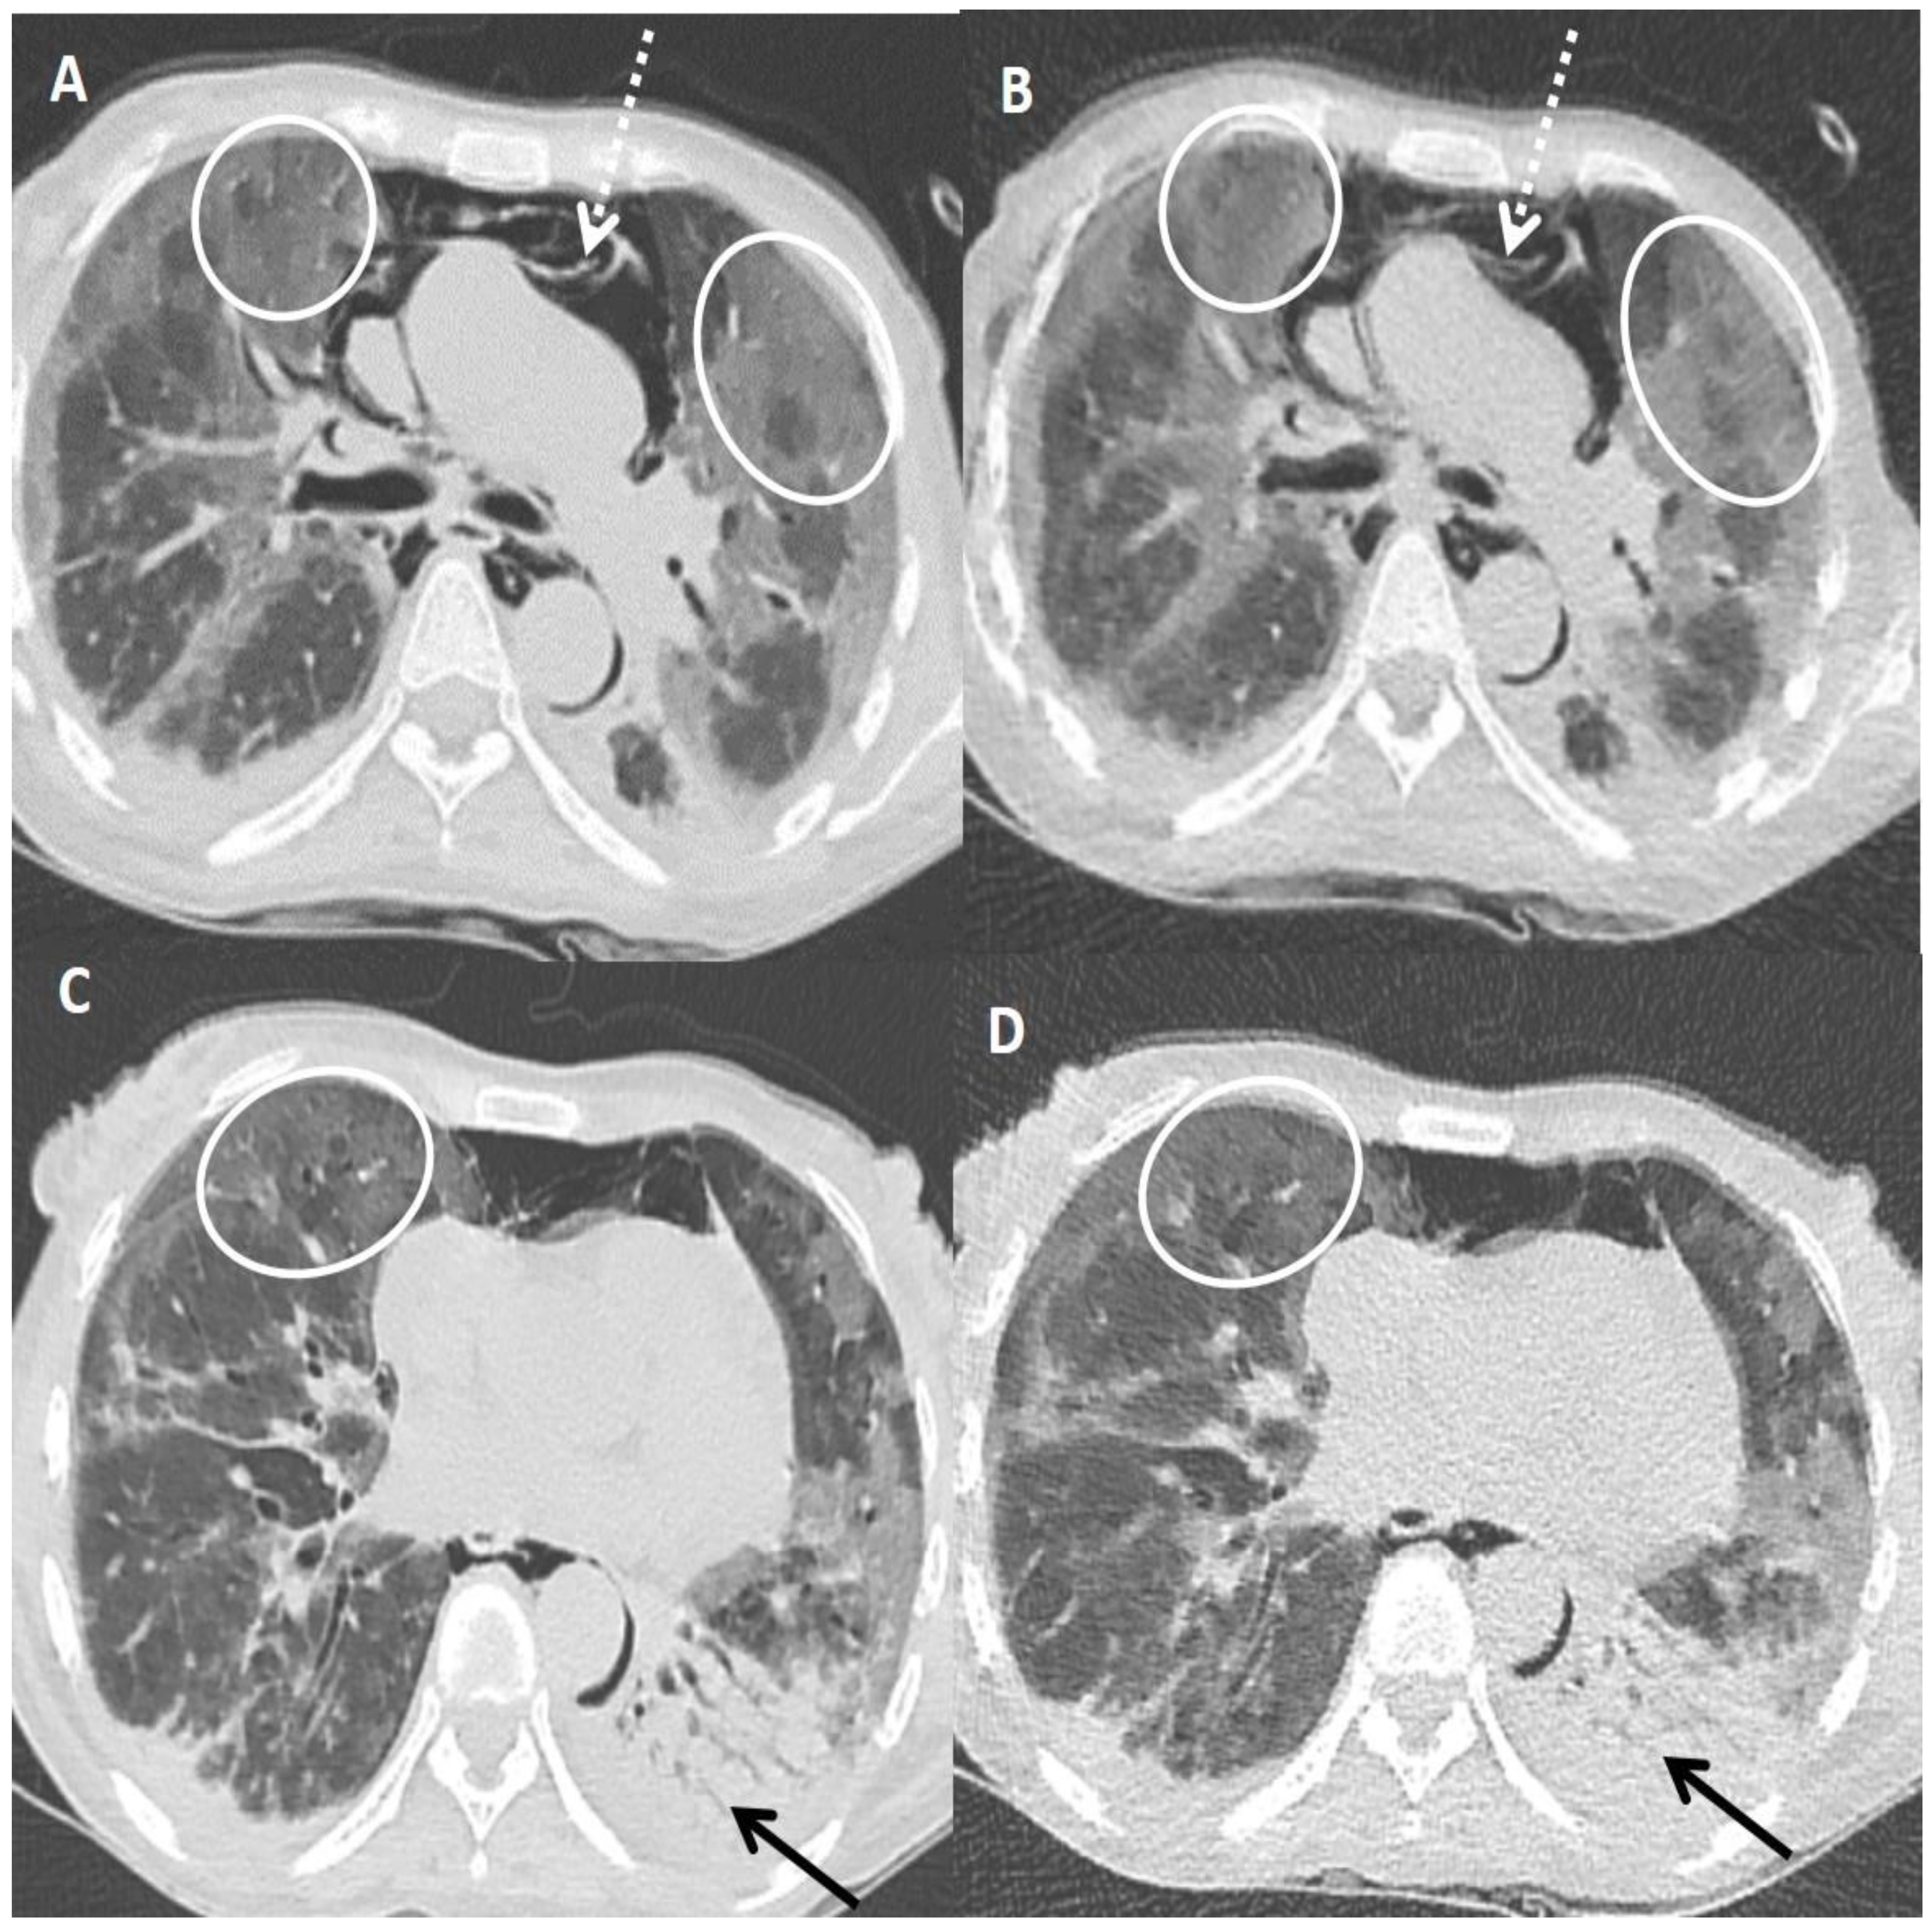

Figure 5.

Fallacies of ultra-low dose CT (ULDCT) chest in two different COVID-19 patients: (A,B) A 53-years old female patient with SDCT (A) showing areas of GGOs in the left lung (black circle) and in the corresponding ULDCT (B) these areas of GGO’s were misinterpreted as consolidation (black circle). (C,D) SDCT images in another patient (C) showing subtle interlobular septal thickening in bilateral lungs (dotted circles) that was missed on the corresponding ULDCT (D) images (dotted circles). CT severity score calculated on SDCT and ULDCT, however, was similar in both patients.